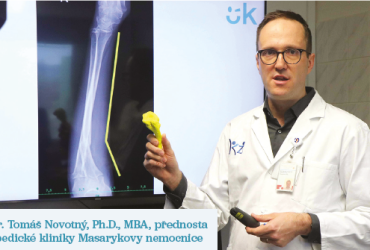

Na Ortopedické klinice v Masarykově nemocnici v Ústí nad Labem odoperovali dvanáctileté pacientce deformovanou loketní kost s využitím technologie 3D tisku a virtuální reality v předoperačním plánování. Příprava proběhla v kooperaci s izraelským partnerem, hlavním světovým lídrem v oblasti nejnovějších medicínských technologií. Spolupráce Krajské zdravotní a izraelského centra bude nadále pokračovat.

Pacientkou byla dívka s deformitou předloktí a porušenou hybností loketního kloubu po dřívější zlomenině. Součástí předoperační přípravy bylo zhotovení 3D modelů kosti, tvorba modelu pro virtuální realitu a konstrukce pro pacientku specifického instrumentária k provedení operace. Díky těmto technologiím byla operace naplánována a provedena s největší přesností. Výkon proběhl ve spolupráci a za podpory Levin Center of Surgical Innovation & 3D Printing, Tel Aviv Sourasky Medical Center – Ichilov, Izrael, které je hlavním světovým pracovištěm v oblasti použití 3D tisku a nejnovějších technologií v medicíně.

„V rámci předoperační přípravy můžeme na našem pracovišti již rutinně operovanou kost vytisknout na 3D tiskárně a deformitu si předem osahat. Díky spolupráci s izraelským pracovištěm jsme se posunuli o další technologický stupeň. V letošním roce jsem zde absolvoval dva studijní pobyty a v rámci naší další spolupráce jsme společně již zahájili a rozplánovali některé projekty. Jedním z nich byla tvorba přesné šablony pro naši pacientku, podle níž jsme během operace kost srovnali ve všech rovinách tak, aby byl loket znovu plně funkční. Bonusem v předoperační přípravě bylo využití virtuální reality, díky níž jsme si s kolegy předem celý zákrok mohli vyzkoušet nanečisto. Zapojením těchto technologií do klinické praxe se dostáváme do pomyslné první ligy ortopedických pracovišť aplikujících do své práce inovace a přinášíme tyto možnosti pacientům našeho kraje. Za to jsem velmi rád a děkuji za podporu jak vedení Krajské zdravotní, tak izraelským tutorům,“ vysvětluje MUDr. Tomáš Novotný, Ph.D., MBA, přednosta Ortopedické kliniky v Masarykově nemocnici v Ústí nad Labem, který operaci provedl.

Výhodou tohoto moderního chirurgického postupu je zkrácení doby operace, zmenšení rozsahu operačního pole a nižší krevní ztráty. Prokazatelně tak lze dosáhnout lepších výsledků a kratší rekonvalescence. Izraelská strana zhotovila podpůrné 3D tisky pro ústeckou Masarykovu nemocnici bezplatně a její participace na operaci je základem pro další spolupráci ve výzkumu a implementaci nejnovějších technologií v České republice, a to také za podpory Velvyslanectví České republiky v Izraeli.

Výhodou tohoto moderního chirurgického postupu je zkrácení doby operace, zmenšení rozsahu operačního pole a nižší krevní ztráty. Prokazatelně tak lze dosáhnout lepších výsledků a kratší rekonvalescence. Izraelská strana zhotovila podpůrné 3D tisky pro ústeckou Masarykovu nemocnici bezplatně a její participace na operaci je základem pro další spolupráci ve výzkumu a implementaci nejnovějších technologií v České republice, a to také za podpory Velvyslanectví České republiky v Izraeli.